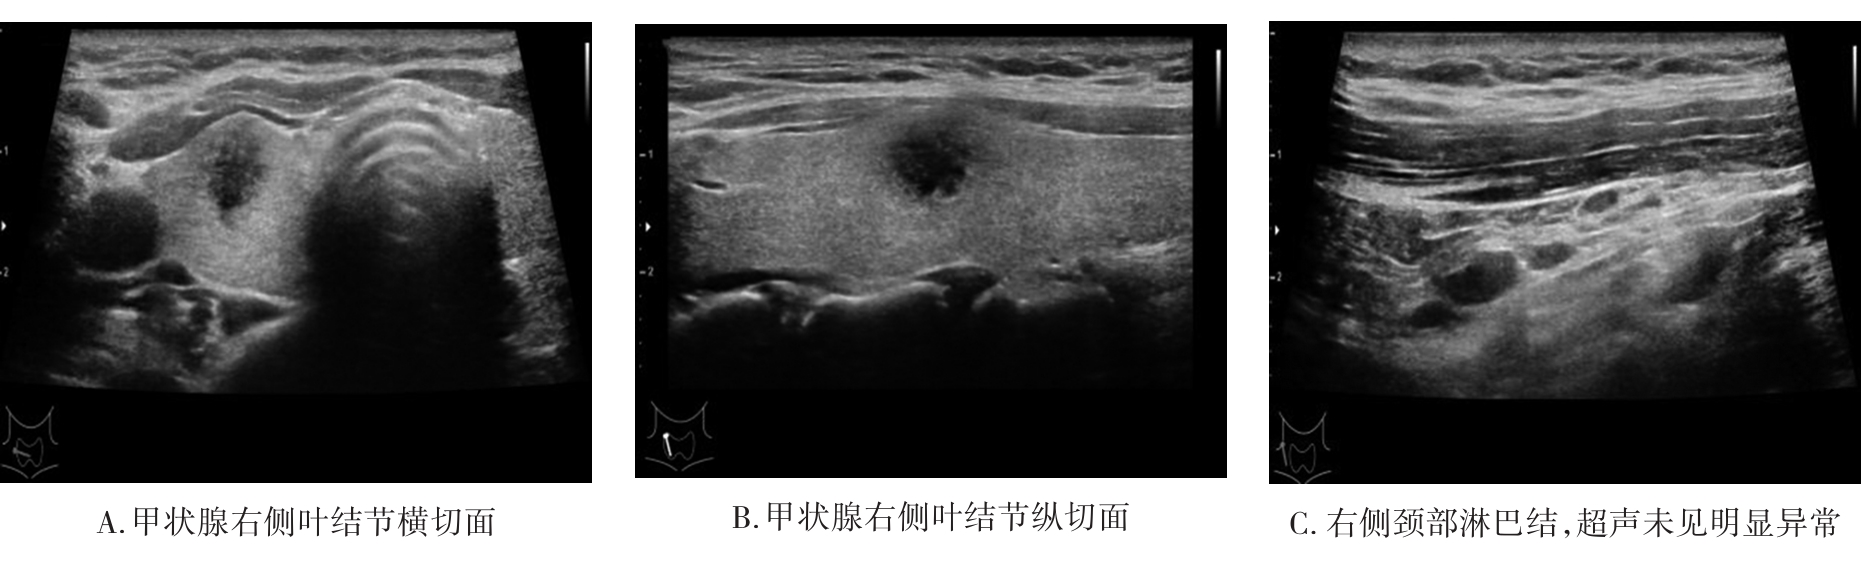

• 基于SEER数据库构建高危PTMC的诊断模型与验证

2023, 48(12):1418-1424. DOI: 10.13406/j.cnki.cyxb.003392

摘要 (71) HTML (47) PDF 1.64 M (177) 评论 (0) 收藏

摘要:目的 探讨高危甲状腺微小乳头状癌(papillary thyroid microcarcinoma,PTMC)的风险预测因子,构建可靠的列线图诊断模型并验证。方法 回顾性分析2004至2015年SEER数据库中手术治疗的PTMC患者(训练集)以及2020至2022年四川省人民医院甲状腺诊疗中心诊治的甲状腺微小结节患者(外部验证集)的临床病理及超声影像资料。验证集中,利用logistic回归分析高危PTMC的风险预测因子,构建列线图诊断模型并采用内部验证集和外部验证集分别进行验证。再根据术前超声影像学特征进行间接评估,探讨术前超声影像学特征预测高危PTMC的可行性与可靠性。结果 训练集纳入患者1 552例,外部验证集纳入患者516例。训练集中筛选出高危PTMC的独立危险因素为性别(男性)、年龄(≤55岁)、结节数目(多灶)、包膜侵犯,颈部淋巴结异常(P<0.05),构建出的列线图C指数为0.946。在训练集及外部验证集中,该列线图模型的预测结果与实际情况均具有较好的一致性。基于超声影像特征诊断高危PTMC的受试者工作特征(receiver operating characteristic,ROC)的曲线下面积(area under the curve,AUC)值为0.931(95%CI=0.910~0.953),与基于病理特征诊断的AUC值具有较高的一致性(κ=0.611,P<0.05)。结论 本研究构建的高危PTMC诊断模型具有较好的预测效应,利用术前超声影像学特征预测高危PTMC具有一定的临床可行性及临床应用价值。